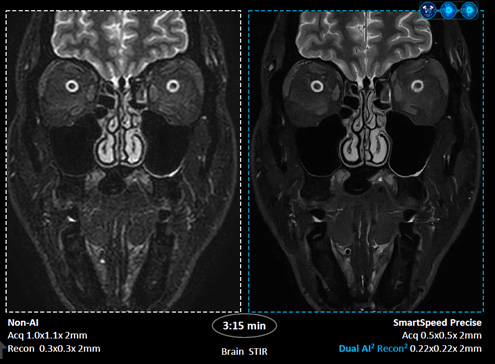

• 좌측은 기존 방식(Non-AI), 우측은 ‘SmartSpeed Precise’를 적용한 뇌 STIR 영상 /이미지 제공=필립스코리아

▲ 좌측은 기존 방식(Non-AI), 우측은 ‘SmartSpeed Precise’를 적용한 뇌 STIR 영상 /이미지 제공=필립스코리아

스마트스피드 프리사이즈는 필립스의 기존 MR 검사 시간 단축 기술 ‘컴프레스드 센스(Compressed SENSE)’에 듀얼 AI 엔진을 적용한 것이 특징이다. 데이터 밸런싱 알고리즘과 AI 재구성 알고리즘을 원시 데이터 단계부터 적용해 핵심 신호만 선별하고 불필요한 노이즈를 제거한다.

회사에 따르면, 이 기술은 기존 대비 최대 3배 빠른 검사 속도를 구현하면서도 영상 선명도를 최대 80%까지 높인다. 초고해상도 알고리즘을 강화해 신호대잡음비(SNR)를 개선하고, 링잉 방지 기능을 더해 영상 품질을 향상시켰다는 설명이다.